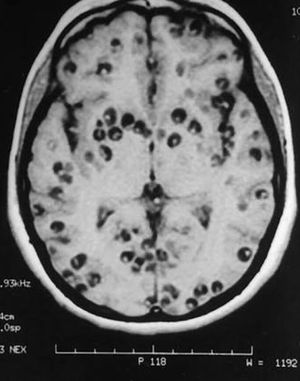

Name this condition.

Yes, it is Neurocysticercosis.

Multiple Neurocysticercosis...and probably Stage II ..

Taeniasis..soleum and saginata..From uncooked pork meats..First affects GI systems then through Systemic circulation In Brain

No Helen, it is Neurocysticercosis grade 2.